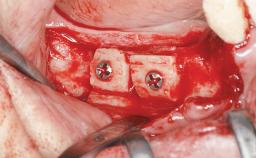

Le Fort I Interpositional Graft and Mandibular Sandwich Osteotomy for Maxillofacial Rehabilitation after Severe Periodontitis

Bone Augmentation Horizontal|Sinus Floor Elevation|Staged|Vertical

Bone Volume Deficient vertically or deficient vertically AND horizontally